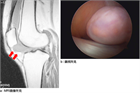

1. 関節水腫の原因となる疾患を、貯留した関節液の性状から、1)非炎症性2)炎症性3)化膿性4)血性の4グループから原因疾患を分類して考える(推奨度2)

1. その原因として、変性疾患、リウマチ性疾患、化膿性疾患、腫瘍性疾患、それに外傷などがある(推奨度2)